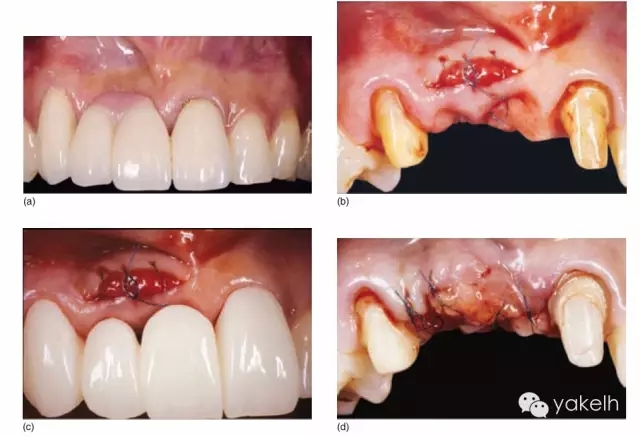

¤¤這類復雜的膜齦手術用于同時處理多個根面Ⅰ類/使Ⅱ類牙齦退縮(圖5.11a~m)。

圖5.11 (a)患者休息放松狀態(tài)下的嘴唇——上下唇不能完全閉合。(b)右上尖牙和側切牙呈Ⅰ類牙齦退縮。(c)左上頜尖牙和側切牙呈Ⅱ類牙齦退縮。(d)先用圓形眼科刀片開始做溝內切口。(e)使用探針在袋內垂直探查貫通隧道,越過膜齦聯(lián)合。(f)使用探針在隧道內橫向探查貫通,保留齦乳頭尖端附著于骨面。(g)從腭部取結締組織移植物,使用絲線牽引,將厚度和大小足夠的結締組織瓣插入隧道內。(h)通過懸吊縫合將組織瓣冠向復位,穩(wěn)定結締組織瓣。(i)術后6個月,上頜右側觀。(j)上頜左側觀,可見牙齦厚度以及色澤的協(xié)調性均得到改善。(k)術后6個月正面觀,牙敏感癥狀消失。(l)術后1年的全口影像,顯示雙側的牙齦退縮均被完全覆蓋,牙齦邊緣增厚且穩(wěn)定,與釉牙骨質界輪廓一致,也與左側中切牙釉質缺損輪廓一致。(m)患者嶄新的笑容,可見側切牙及尖牙的齦緣無退縮。